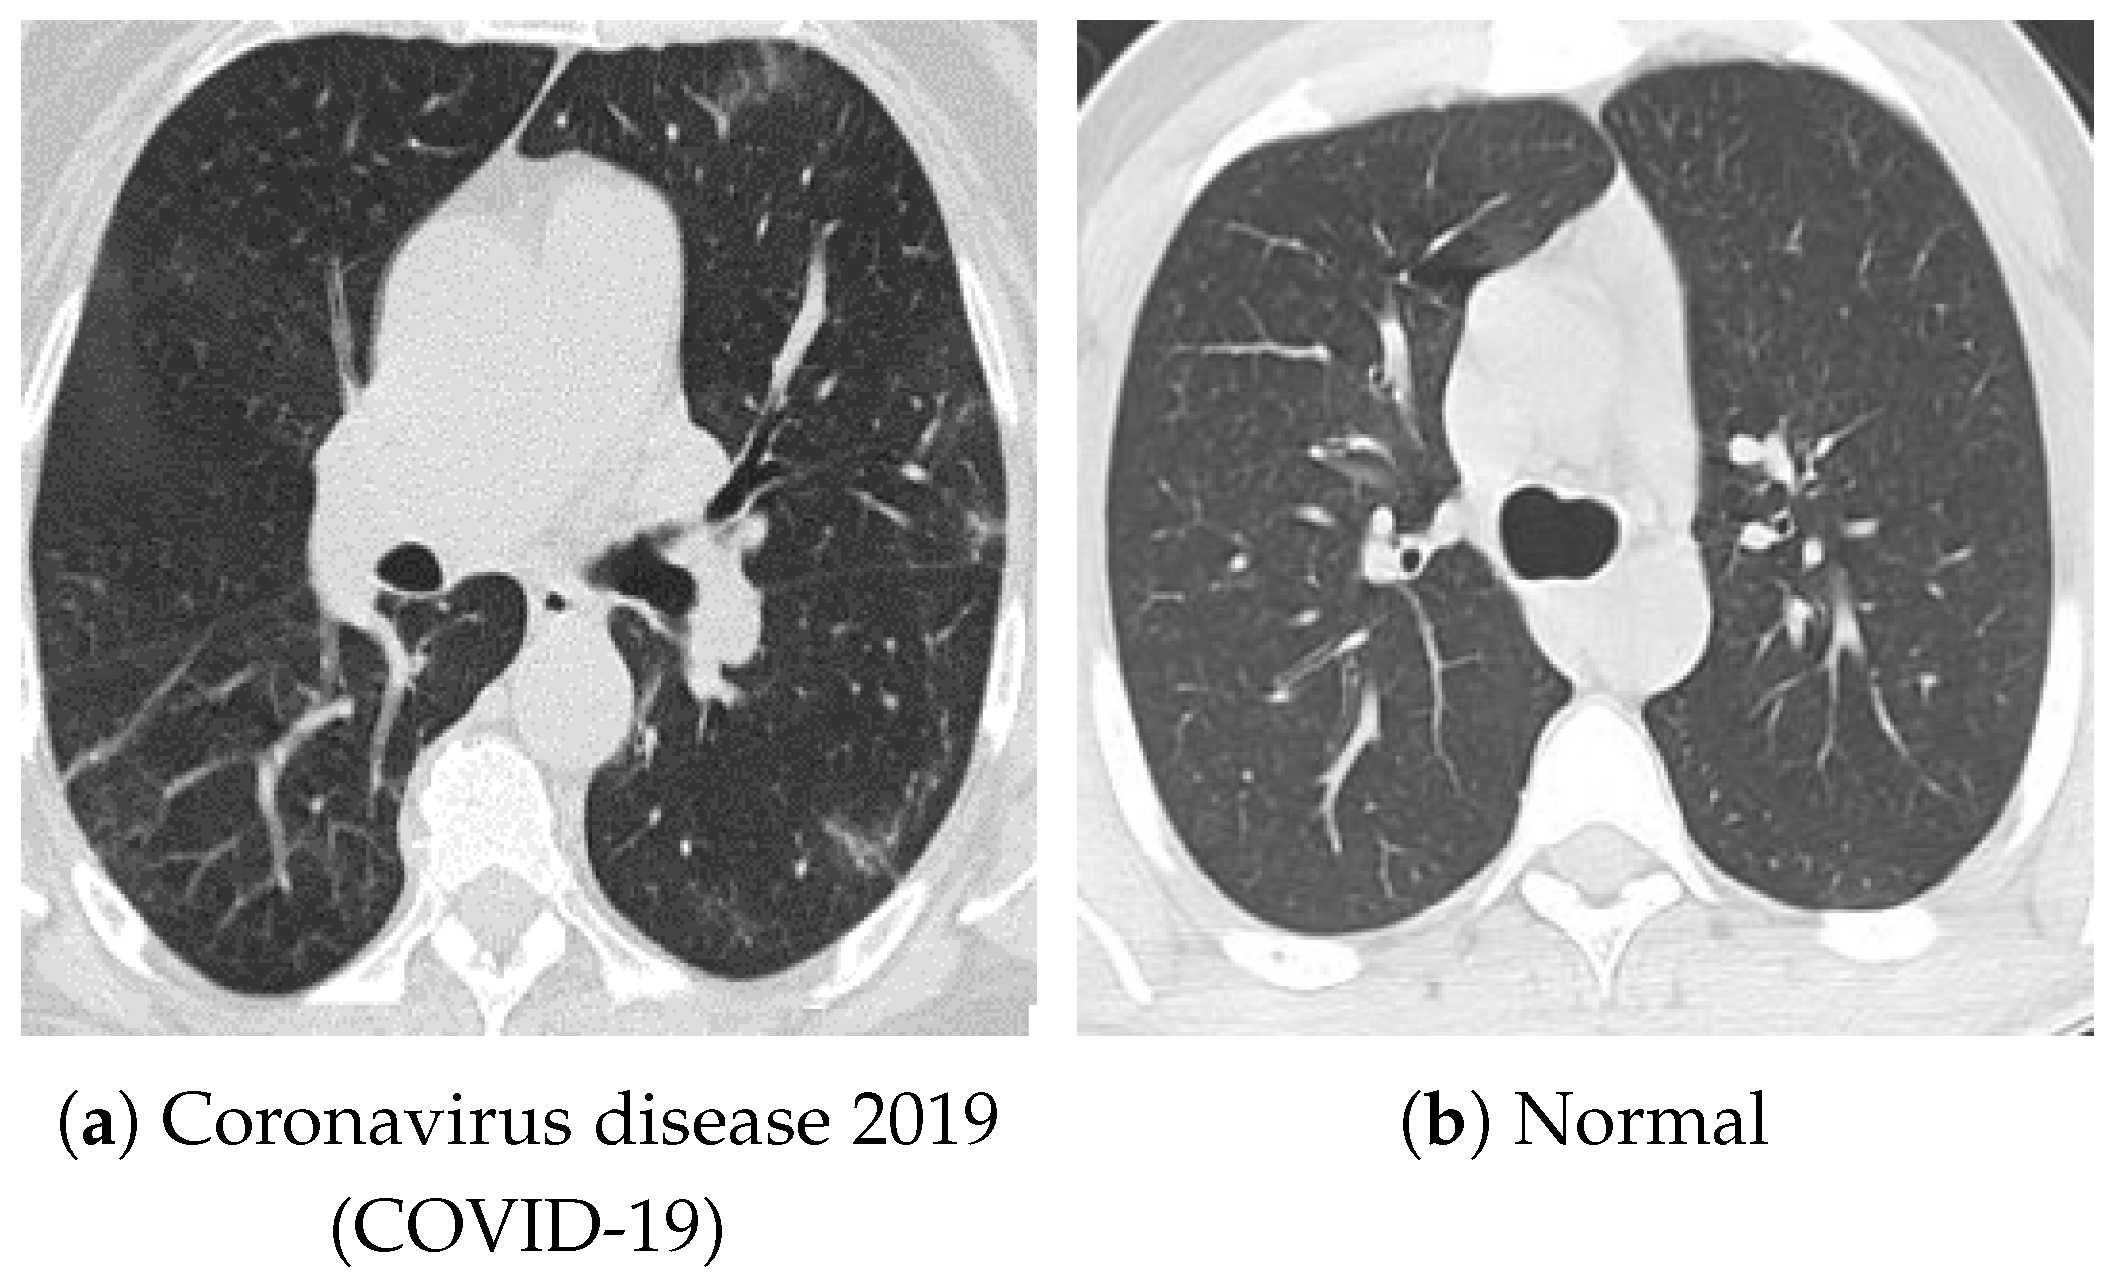

For pretraining, we utilized a subset of the J-MID (https://www.radiology.jp/j-mid/ (accessed on 6 April 2025)) database, which contains large-scale CT scans from Japanese medical institutions, and the RICORD dataset [58], an open dataset that was developed collaboratively by the Radiological Society of North America and international partners and contains chest CT scans collected from four countries. Each dataset was constructed with two domains based on mediastinal and lung window settings in chest CT images. Both domains are denoted as and , and the labels are not used during pretraining. Specifically, for the J-MID subset, (the mediastinal window) contains 31,256 CT images, and (the lung window) contains 26,403 CT images. The RICORD dataset comprises 12,897 (mediastinal window) images and 11,668 (lung window) images for pretraining. For the J-MID dataset, was generated using a window level (WL) of HU and a window width (WW) of HU, whereas was generated using a WL of HU and a WW of HU. For the RICORD dataset, was generated with a WL of HU and a WW of HU, while was generated with a WL of HU and a WW of HU. These parameter ranges were selected to cover clinically standard lung and mediastinal window settings while accommodating inter-scan variability in DICOM metadata. The corresponding images for each example are shown in Figure 2 and Figure 3. For fine-tuning and evaluation, we utilized two public datasets: the SARS-CoV-2 CT-Scan Dataset [59] and the Chest CT-Scan Images Dataset (https://www.kaggle.com/datasets/mohamedhanyyy/chest-ctscan-images (accessed on 6 April 2025)). Both datasets were used for the coronavirus disease 2019 (COVID-19) and chest cancer classification tasks, respectively. The data breakdown is as follows: the SARS-CoV-2 CT-Scan Dataset comprises 1589 training, 397 validation, and 495 test images, labeled into two (COVID-19 and Normal) classes. The Chest CT-Scan Images Dataset comprises 490 training, 123 validation, and 315 test images labeled into four (adenocarcinoma, large-cell carcinoma, squamous-cell carcinoma, and normal) classes. COVID-19 classification and lung cancer classification were selected as downstream tasks because chest CT is widely used in clinical practice for diagnosing both COVID-19 and lung cancer, allowing for an evaluation that closely reflects real-world clinical scenarios. Accordingly, to ensure reproducibility and enable fair comparisons with prior studies, we prioritized the use of publicly available datasets. The corresponding images for each example are shown in Figure 4 and Figure 5.

Figure 4.

Examples of chest CT images on the SARS-CoV-2 CT-Scan dataset: (a) COVID-19 and (b) Normal.